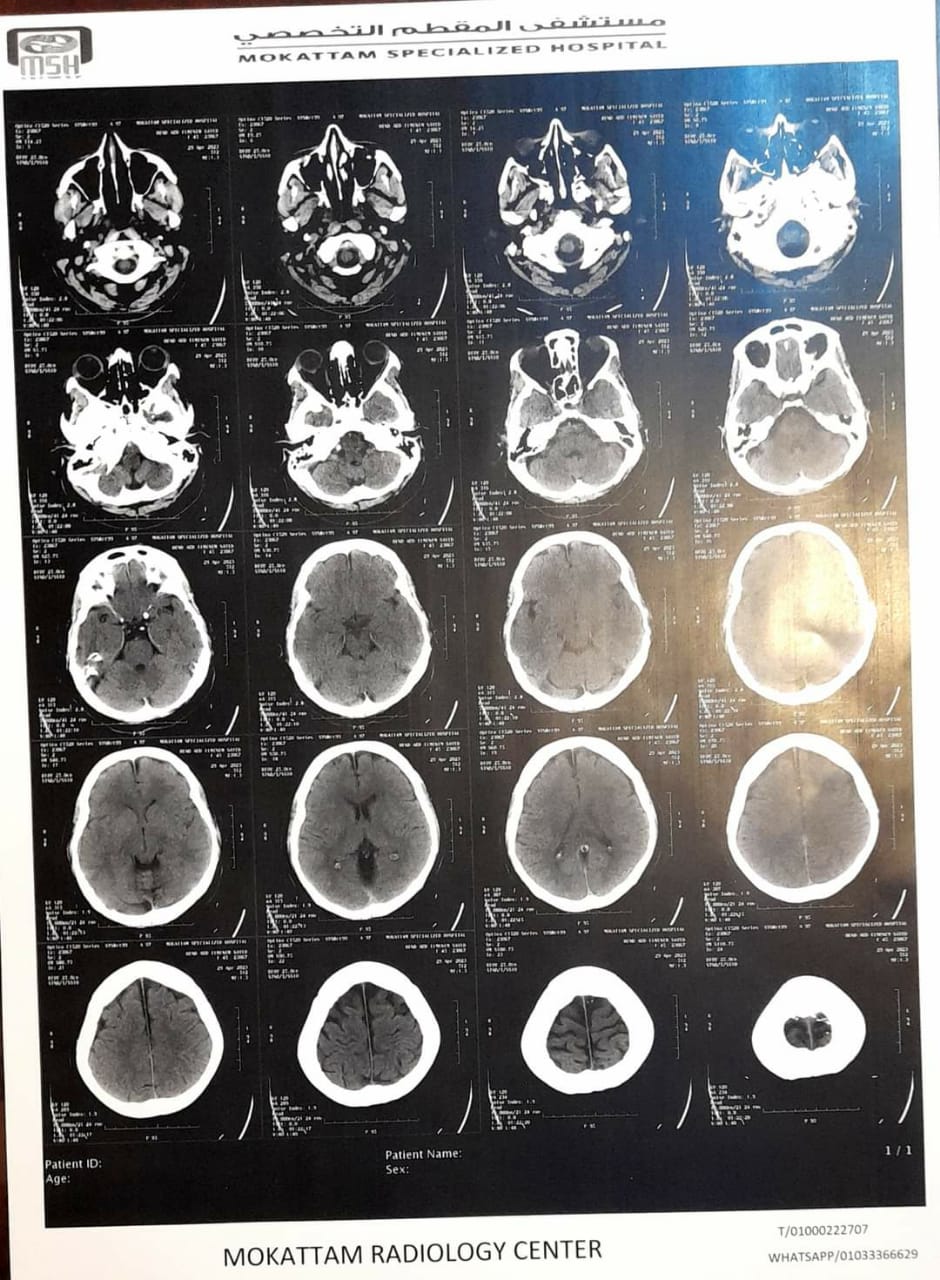

وتابع: توجهنا إلى مستشفى المقطم التخصصي لإتخاذ اللازم والاطمئنان عليها وتم عمل إشاعة مقطعية والحمد لله تبين بعض الكدامات الشديدة بالرأس فقط الحمد لله.

واختتم: وقد أمر الأطباء بالعلاج لمدة ٤ أيام والراحة التامة، ألف حمد وشكر ليك يا رب، اتقدم الشكر للأطباء وشرطة المقطم والأصدقاء على تعاونهم معنا.